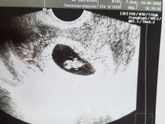

Ура, ура, меня сегодня наконец то поставили на учееет. С начала мая начала ходить на прием к своей гине на участок, уже кучу анализов сдала, некоторые даже по второму кругу и так же позади уже 4 шт узи. Жду теперь снетерпением 13 июля т к будет первый … Читать далее